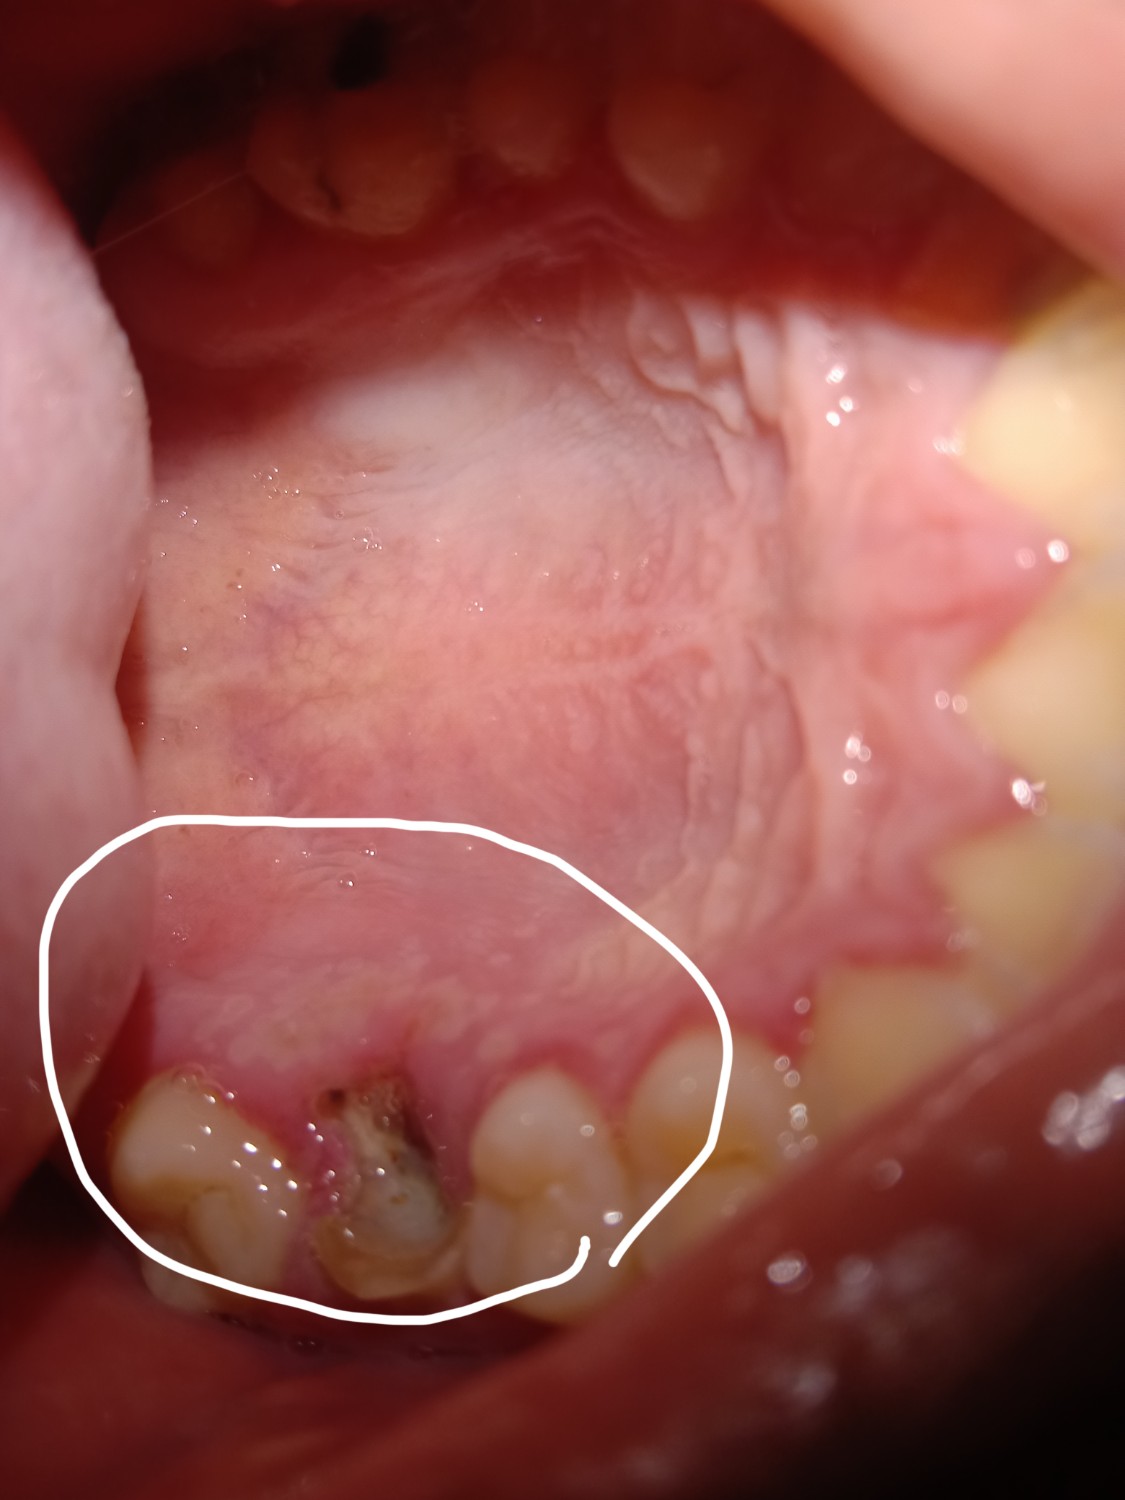

เป็นตุ่มแบบนี้เป็นอะไรคะ